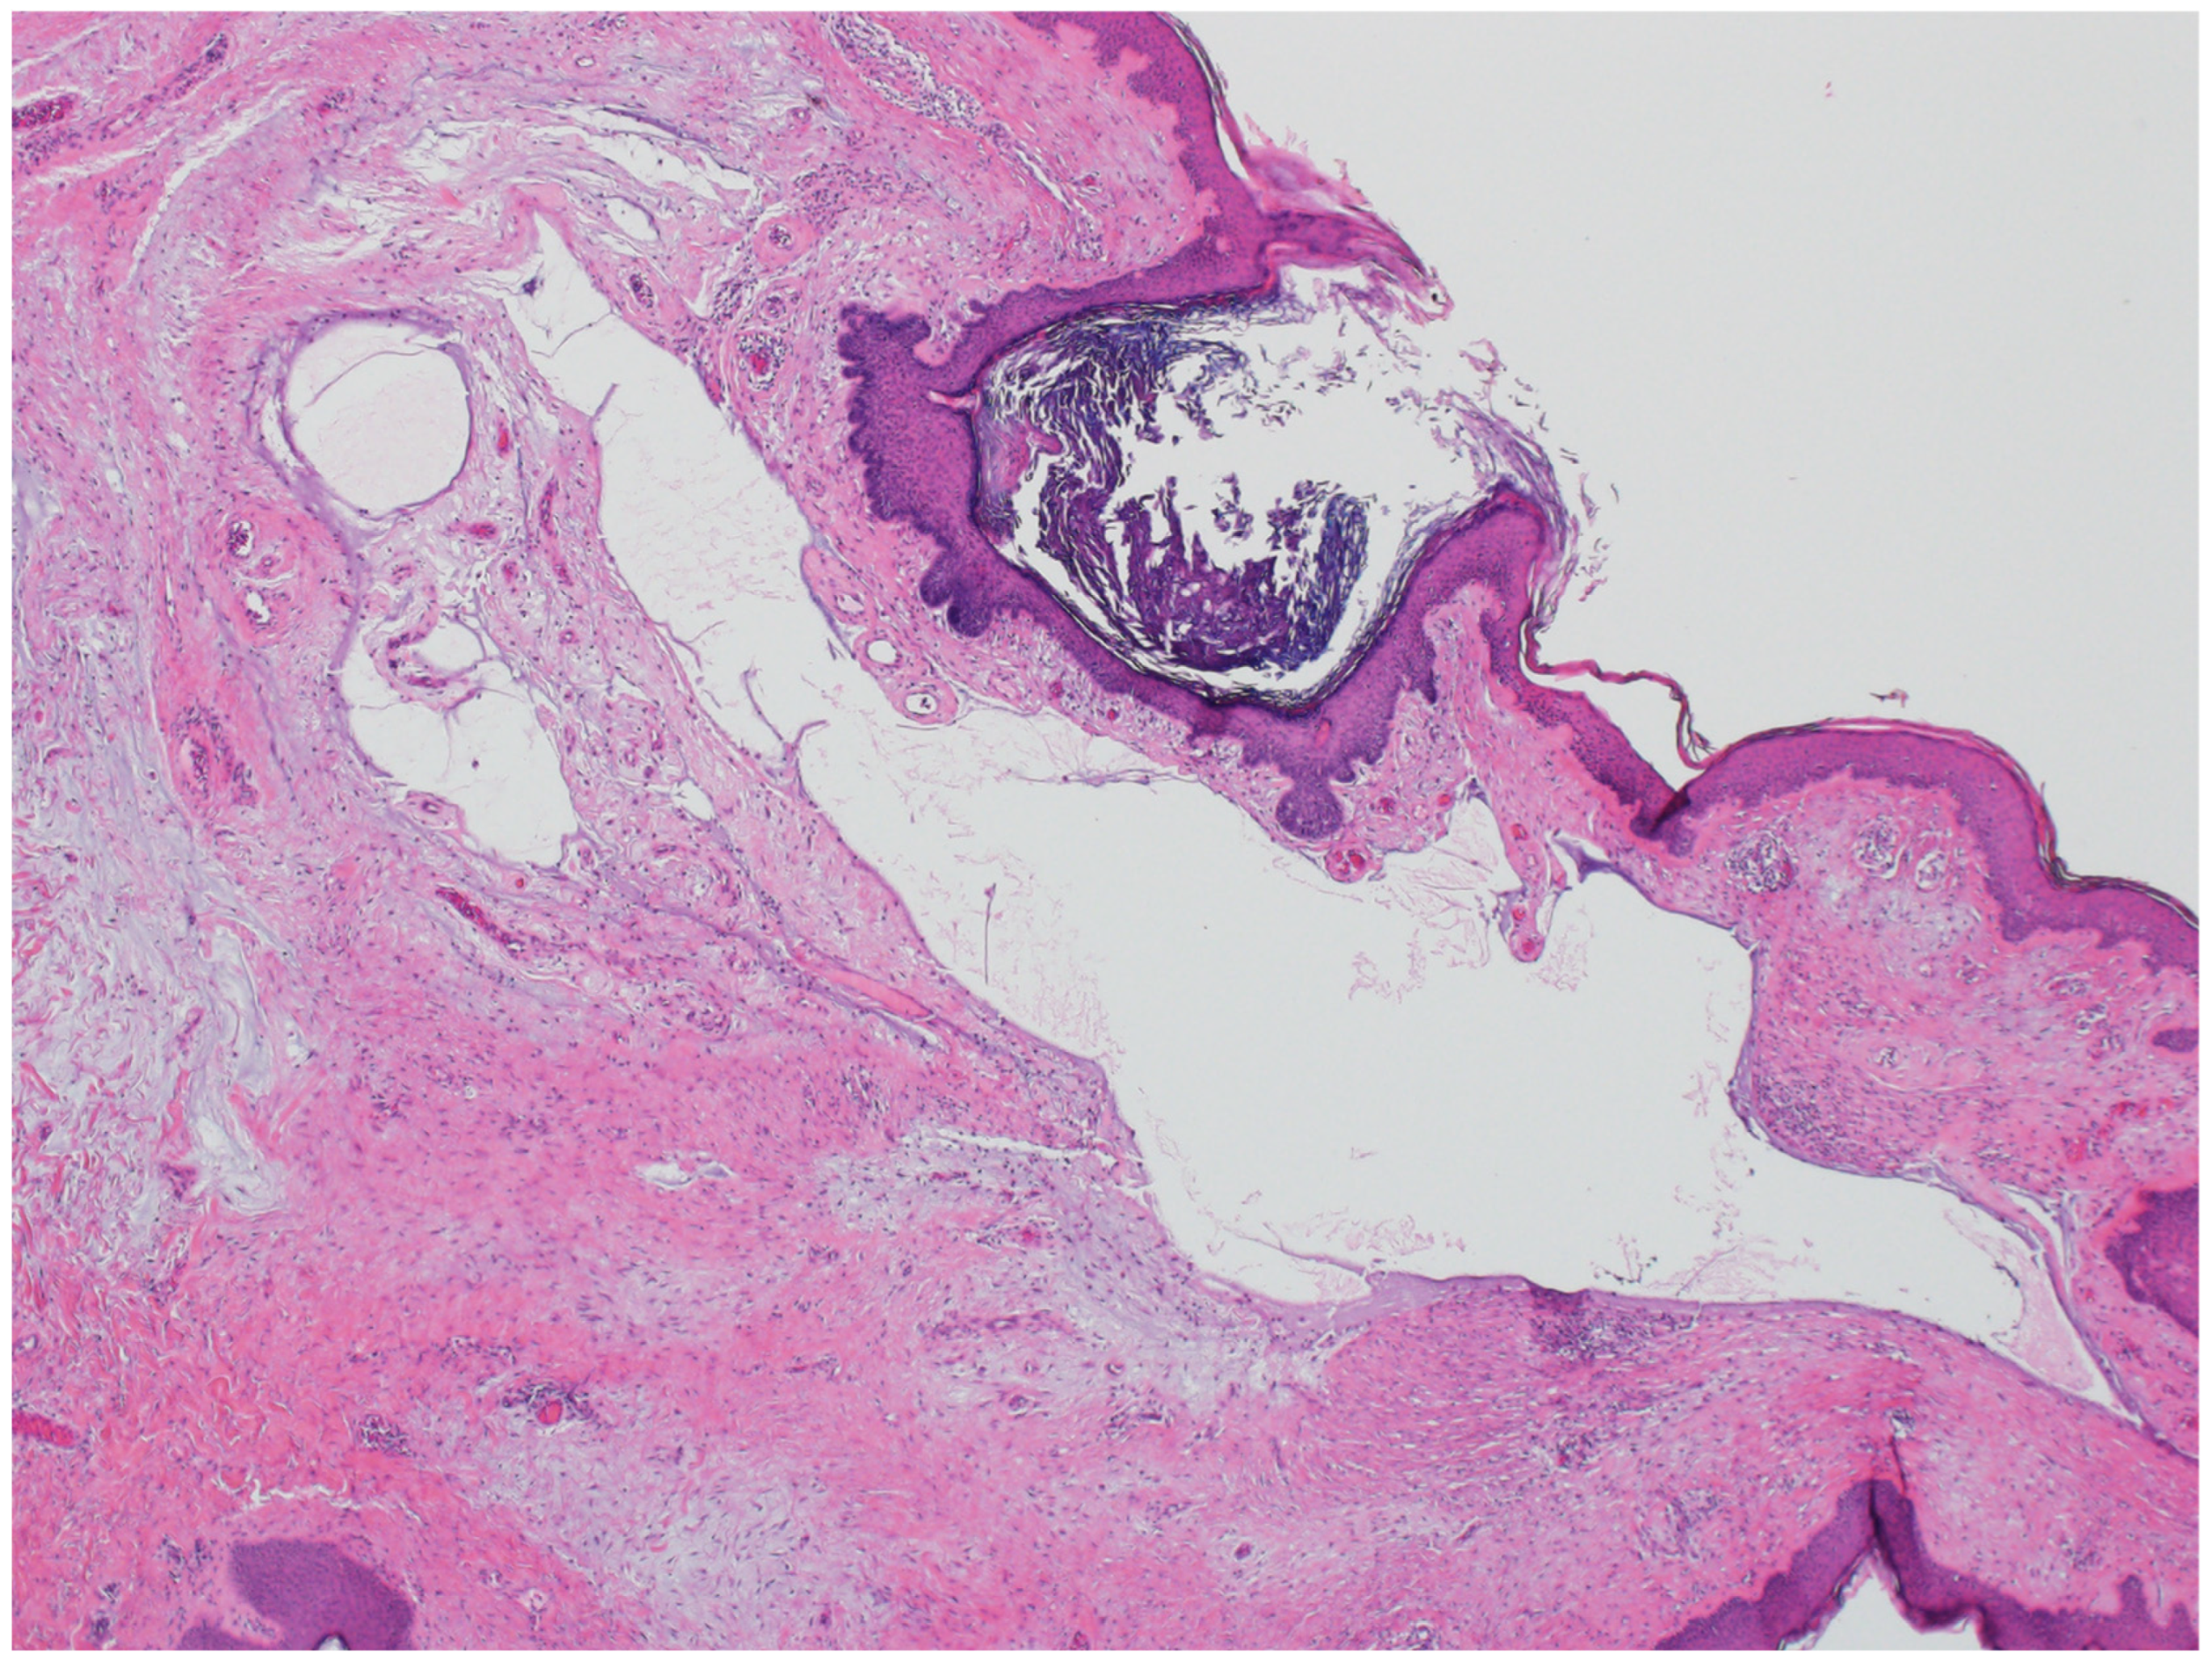

2.5. Basaloid Follicular Hamartoma